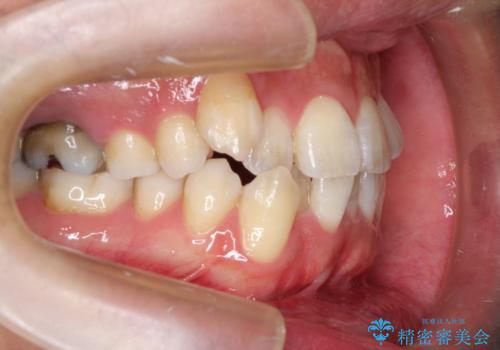

初診時の歯並びの状態としては、右上の犬歯がいわゆる八重歯の状態であり、強いガタガタが上下ともにある状態でした。

スペースの不足量が多く、抜歯を伴うワイヤー矯正にて治療を行いました。

若干の口元の突出感もあったため、抜歯によるスペースを利用し、がたつきの改善と前歯の後退をを行いました。